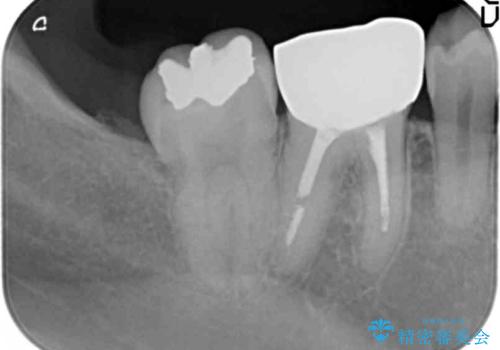

右下の奥の銀歯も治療しています。

- 115.5万円 矯正治療 85万円、奥歯ジルコニアクラウン11万円(ZrCr 10万円、仮歯1万円、矯正用仮歯2万円)セラミックインレー7万円費用は治療当時の料金となります

下の前歯を下げるため、IPR(歯をわずかに削る処置)を行っています。